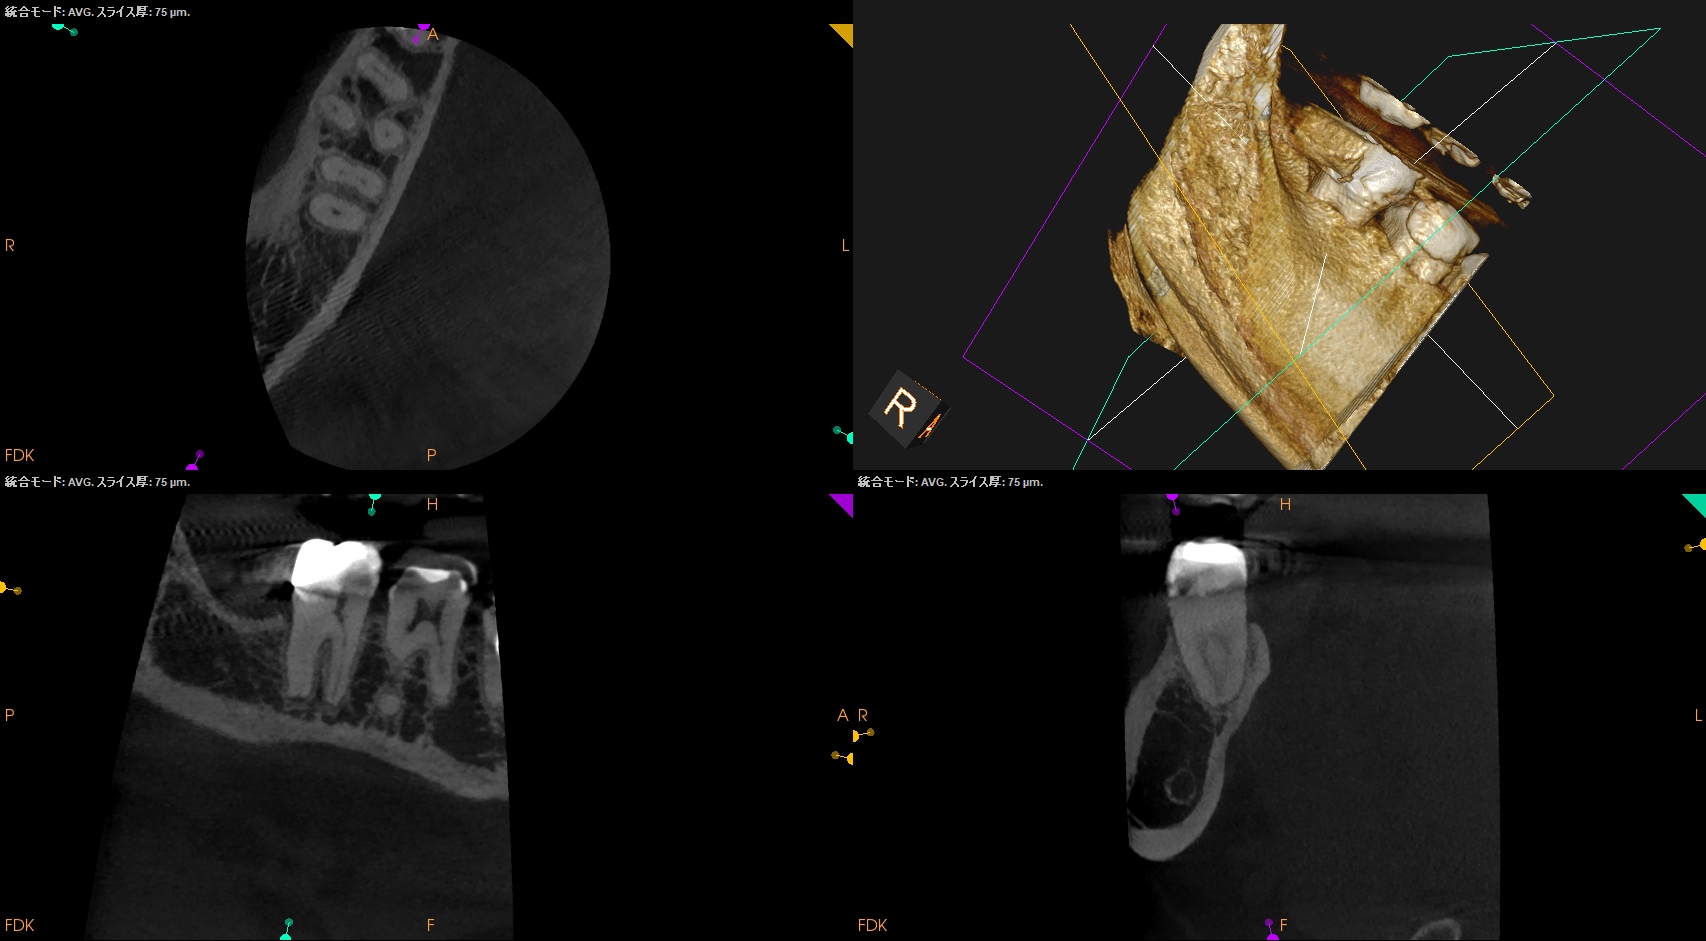

術後にPA, CBCTを撮影した。

MB

ML

D

問題はないだろう。